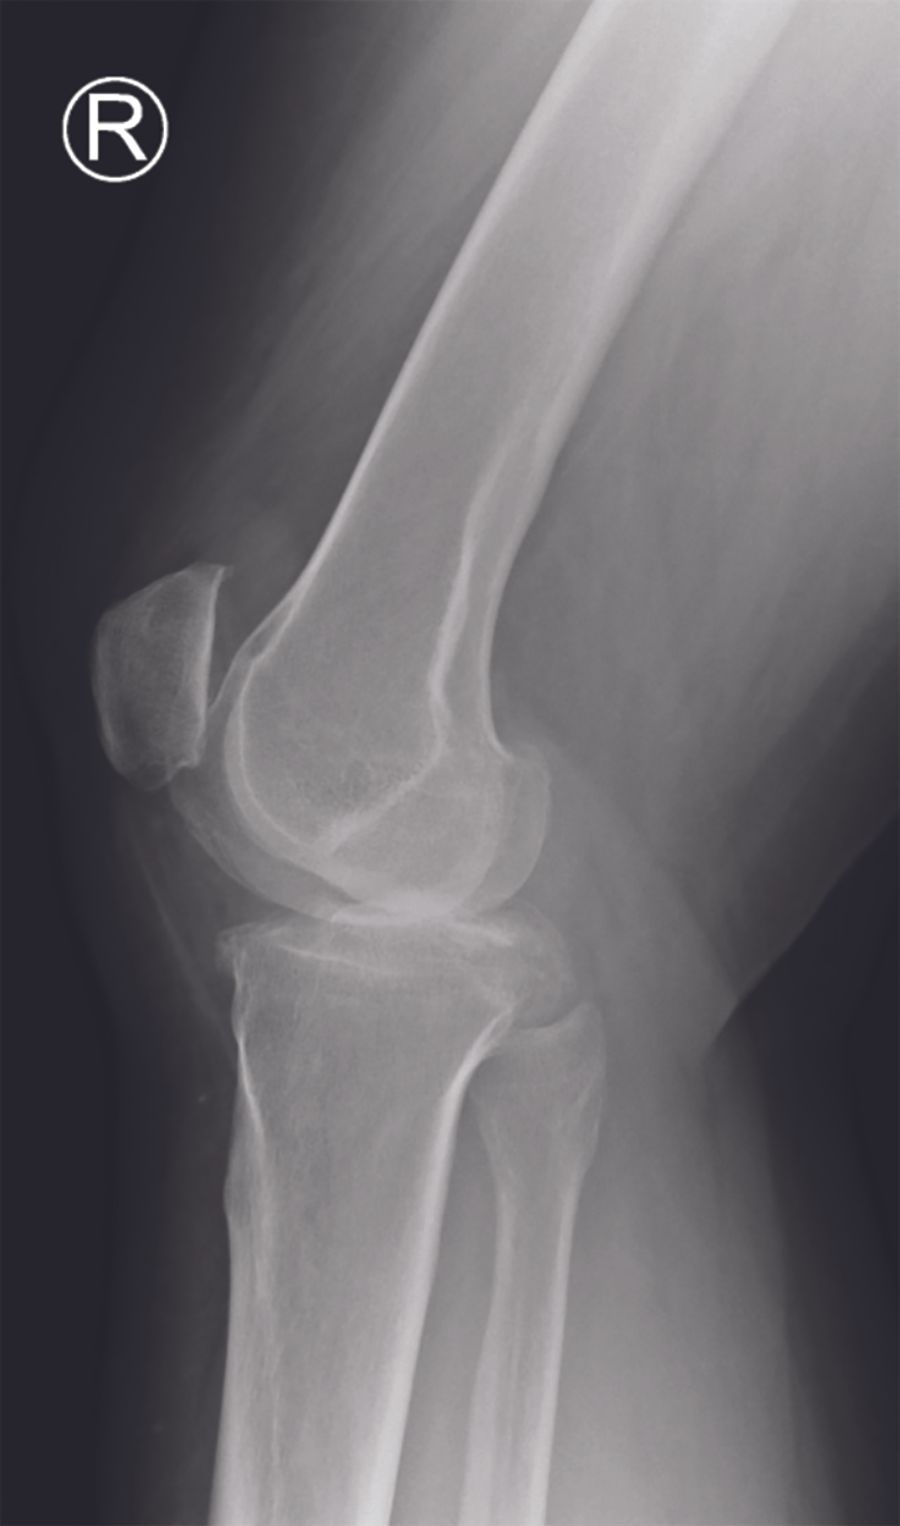

Radiographic assessment (fig. 1A-C)

My routine radiographic examinations of patients referred with pain believed to origin from knee OA include weight-bearing AP, lateral, and skyline views. These may be supplemented by valgus and varus stress radiographs, a Rosenberg view and / or MRI of the knee as needed. It is fundamental to establish bone-on-bone OA in the lateral compartment. Due to the specific features of lateral compartment OA bone-on-bone may not present on the weight-bearing radiograph with the knee extended. If there is any doubt about the bone-on-bone diagnosis in the lateral compartment supplemental imaging should be applied. On the weight-bearing AP view it is also assessed if there is preserved cartilage in the medial compartment. If in doubt a varus-stress radiograph may be helpful to assess this, and at the same time a varus stress will show correction of valgus deformity, opening of the lateral compartment, and indirectly that the LCL is functionally intact. In the lateral radiographic view the relative position of the femur and tibia should be assessed. If the femur is very posteriorly positioned it may be a sign that the ACL is degenerative and torn. The skyline view is specifically assessed for the presence of severe bone-on –bone OA. In general I only find MRI examination necessary in younger patients, particularly if the knee hos posttraumatic OA, in which case MRI can give good information about cartilage damage and degeneration in the lateral and the remaining compartments, as well as the status of cruciate ligaments.